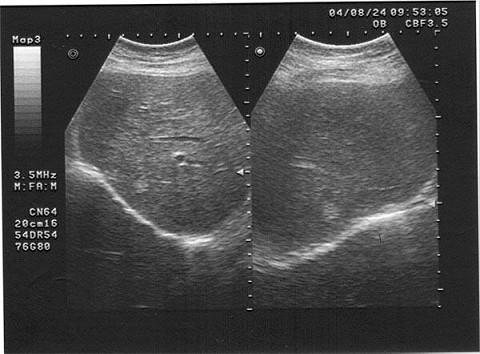

女,40岁,有时右上腹隐痛2年余。结合超声声像图,最可能的诊断为?(?)A.肝血管瘤B.肝脓肿C.小肝癌D.转移性肝癌E.肝囊肿

问题 女,40岁,有时右上腹隐痛2年余。结合超声声像图,最可能的诊断为?(?)

选项 A.肝血管瘤 B.肝脓肿 C.小肝癌 D.转移性肝癌 E.肝囊肿

答案 A